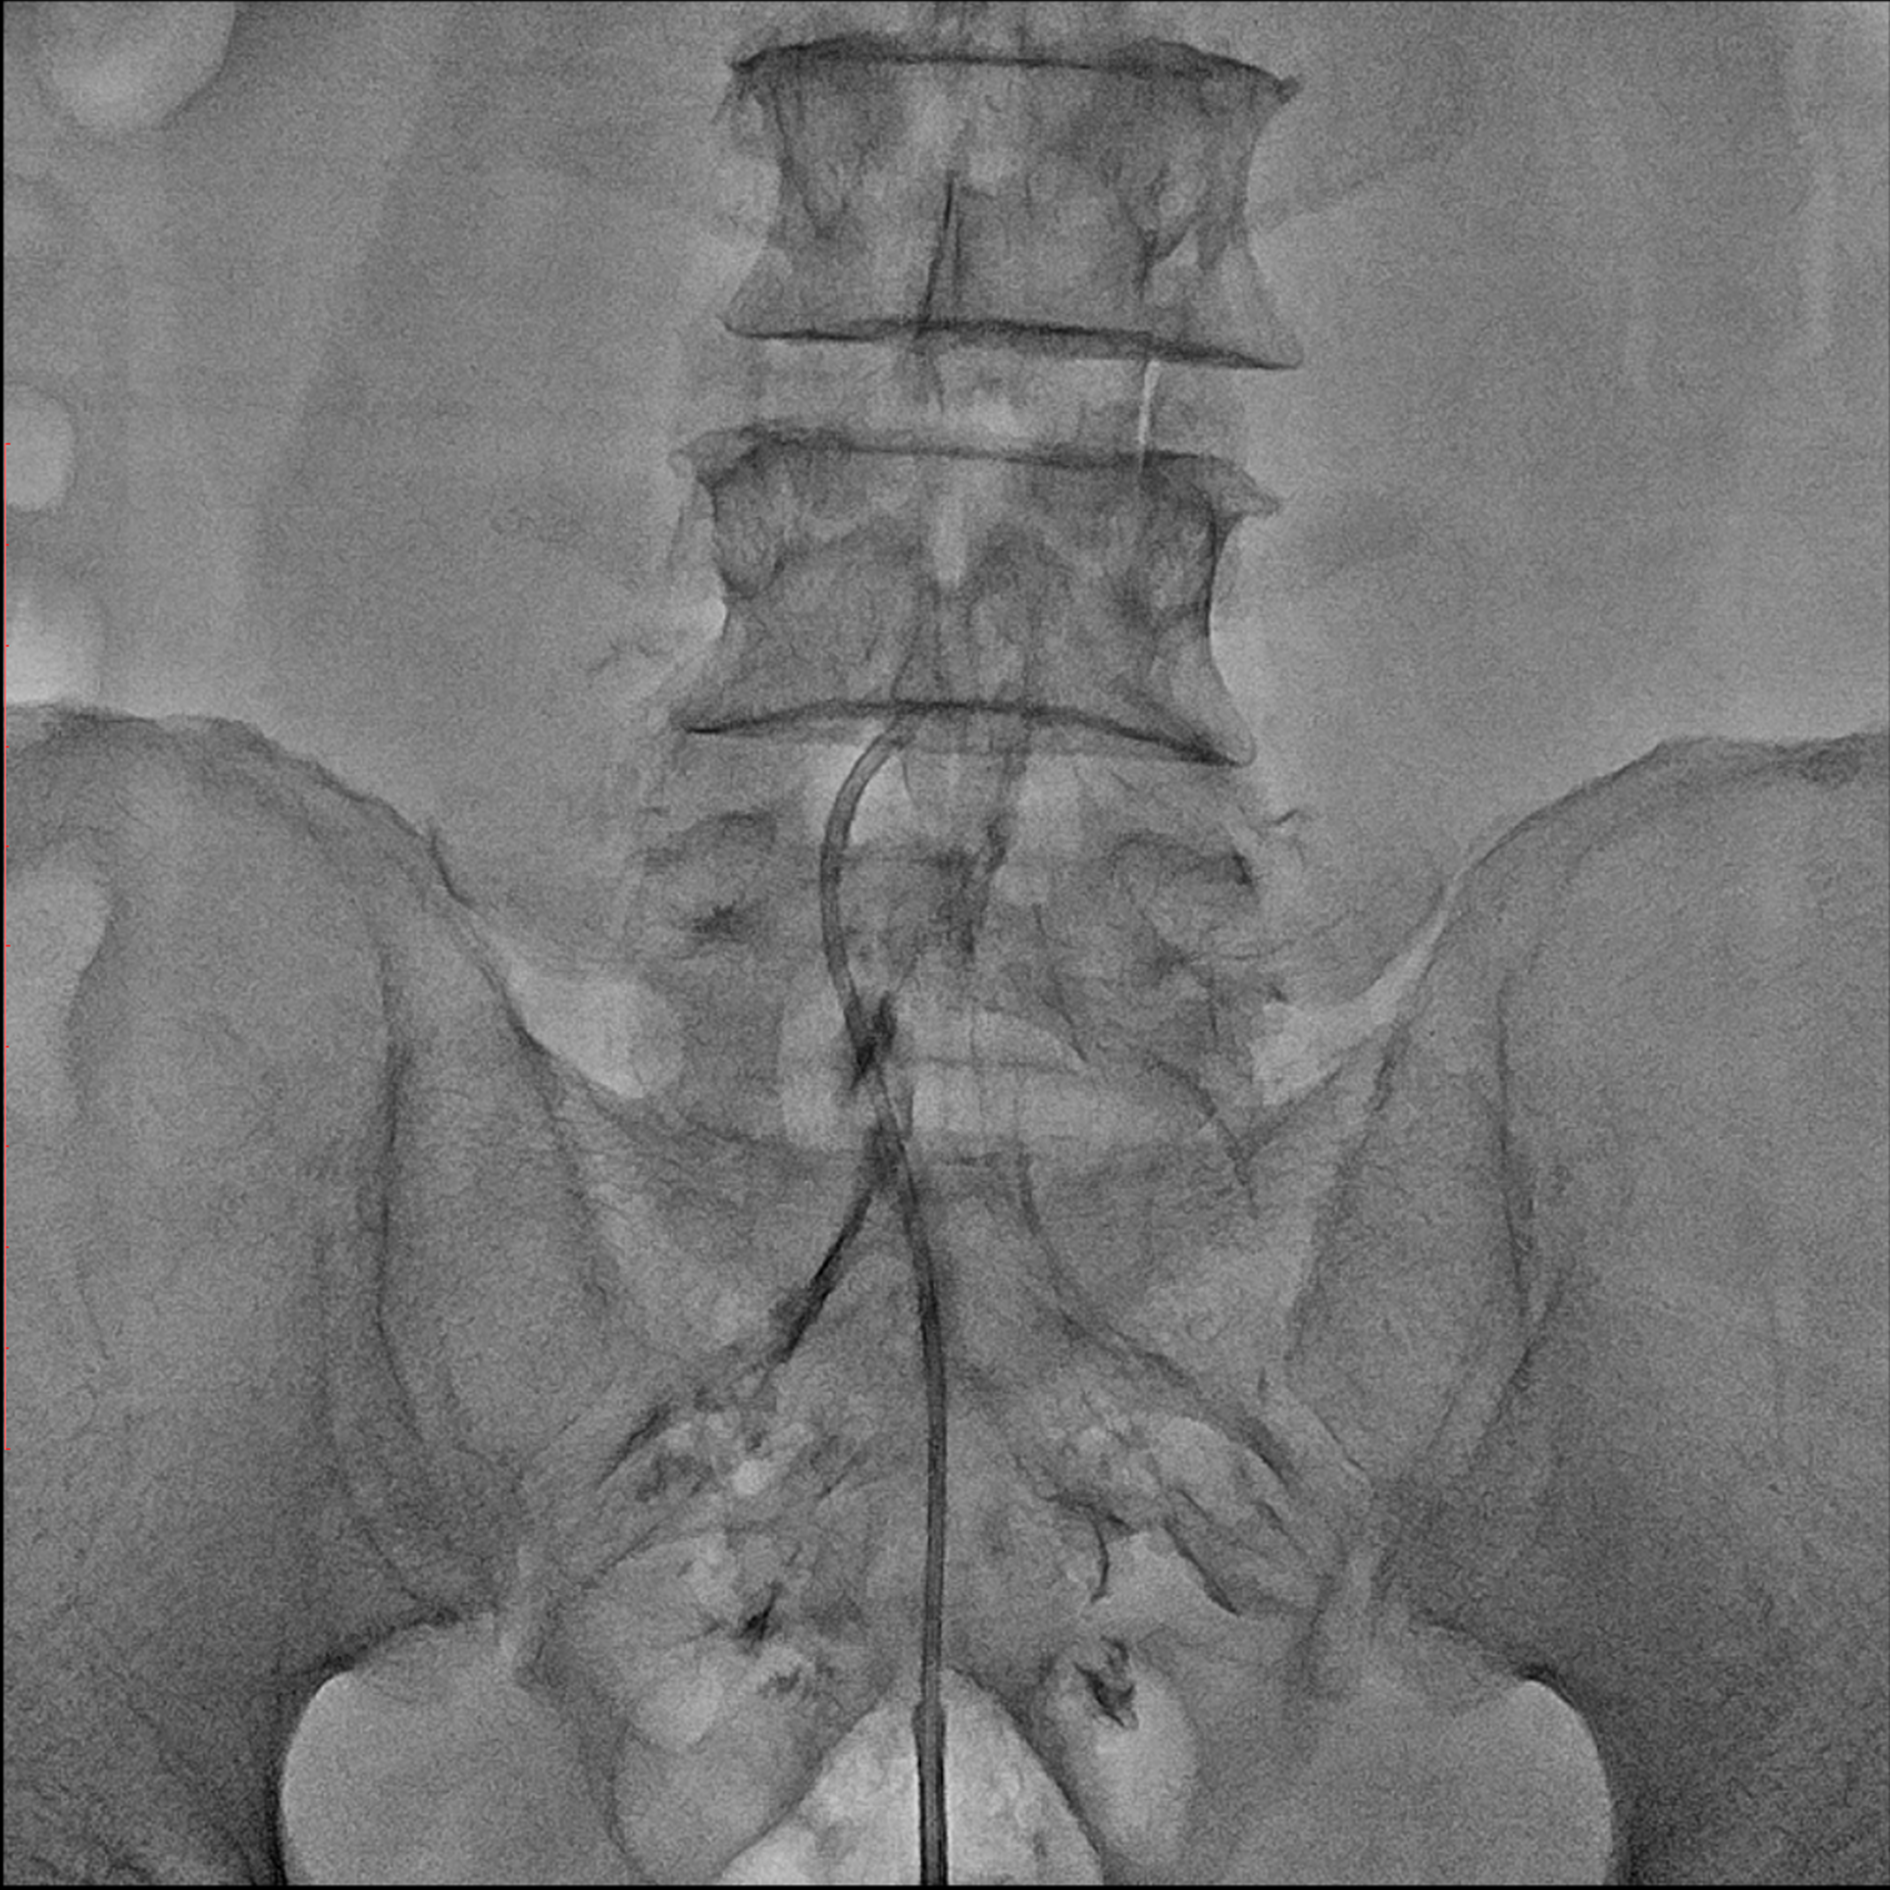

Editorial/Editor's Pick 경막외 유착박리술, Epidural Neuroplasty by Pharmacopuncture Research Lab 2026. 1. 3. 공유하기 게시글 관리 Acupuncture Radiology 관련글 MRI 요양급여의 적용기준 및 방법에 관한 세부사항 MRI 요양급여의 적용기준 및 방법에 관한 세부사항 [신구대조표] Association of AI‑determinedKellgren–Lawrence grade Portable X-ray